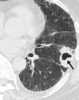

Rheumatoid lung disease is a disease of the lung associated with RA, rheumatoid arthritis. Rheumatoid lung disease is characterized by pleural effusion, pulmonary fibrosis, lung nodules and pulmonary hypertension. [Source: Wikipedia ]

Interstitial lung fibrosis

Widespread small irregular lung opacities